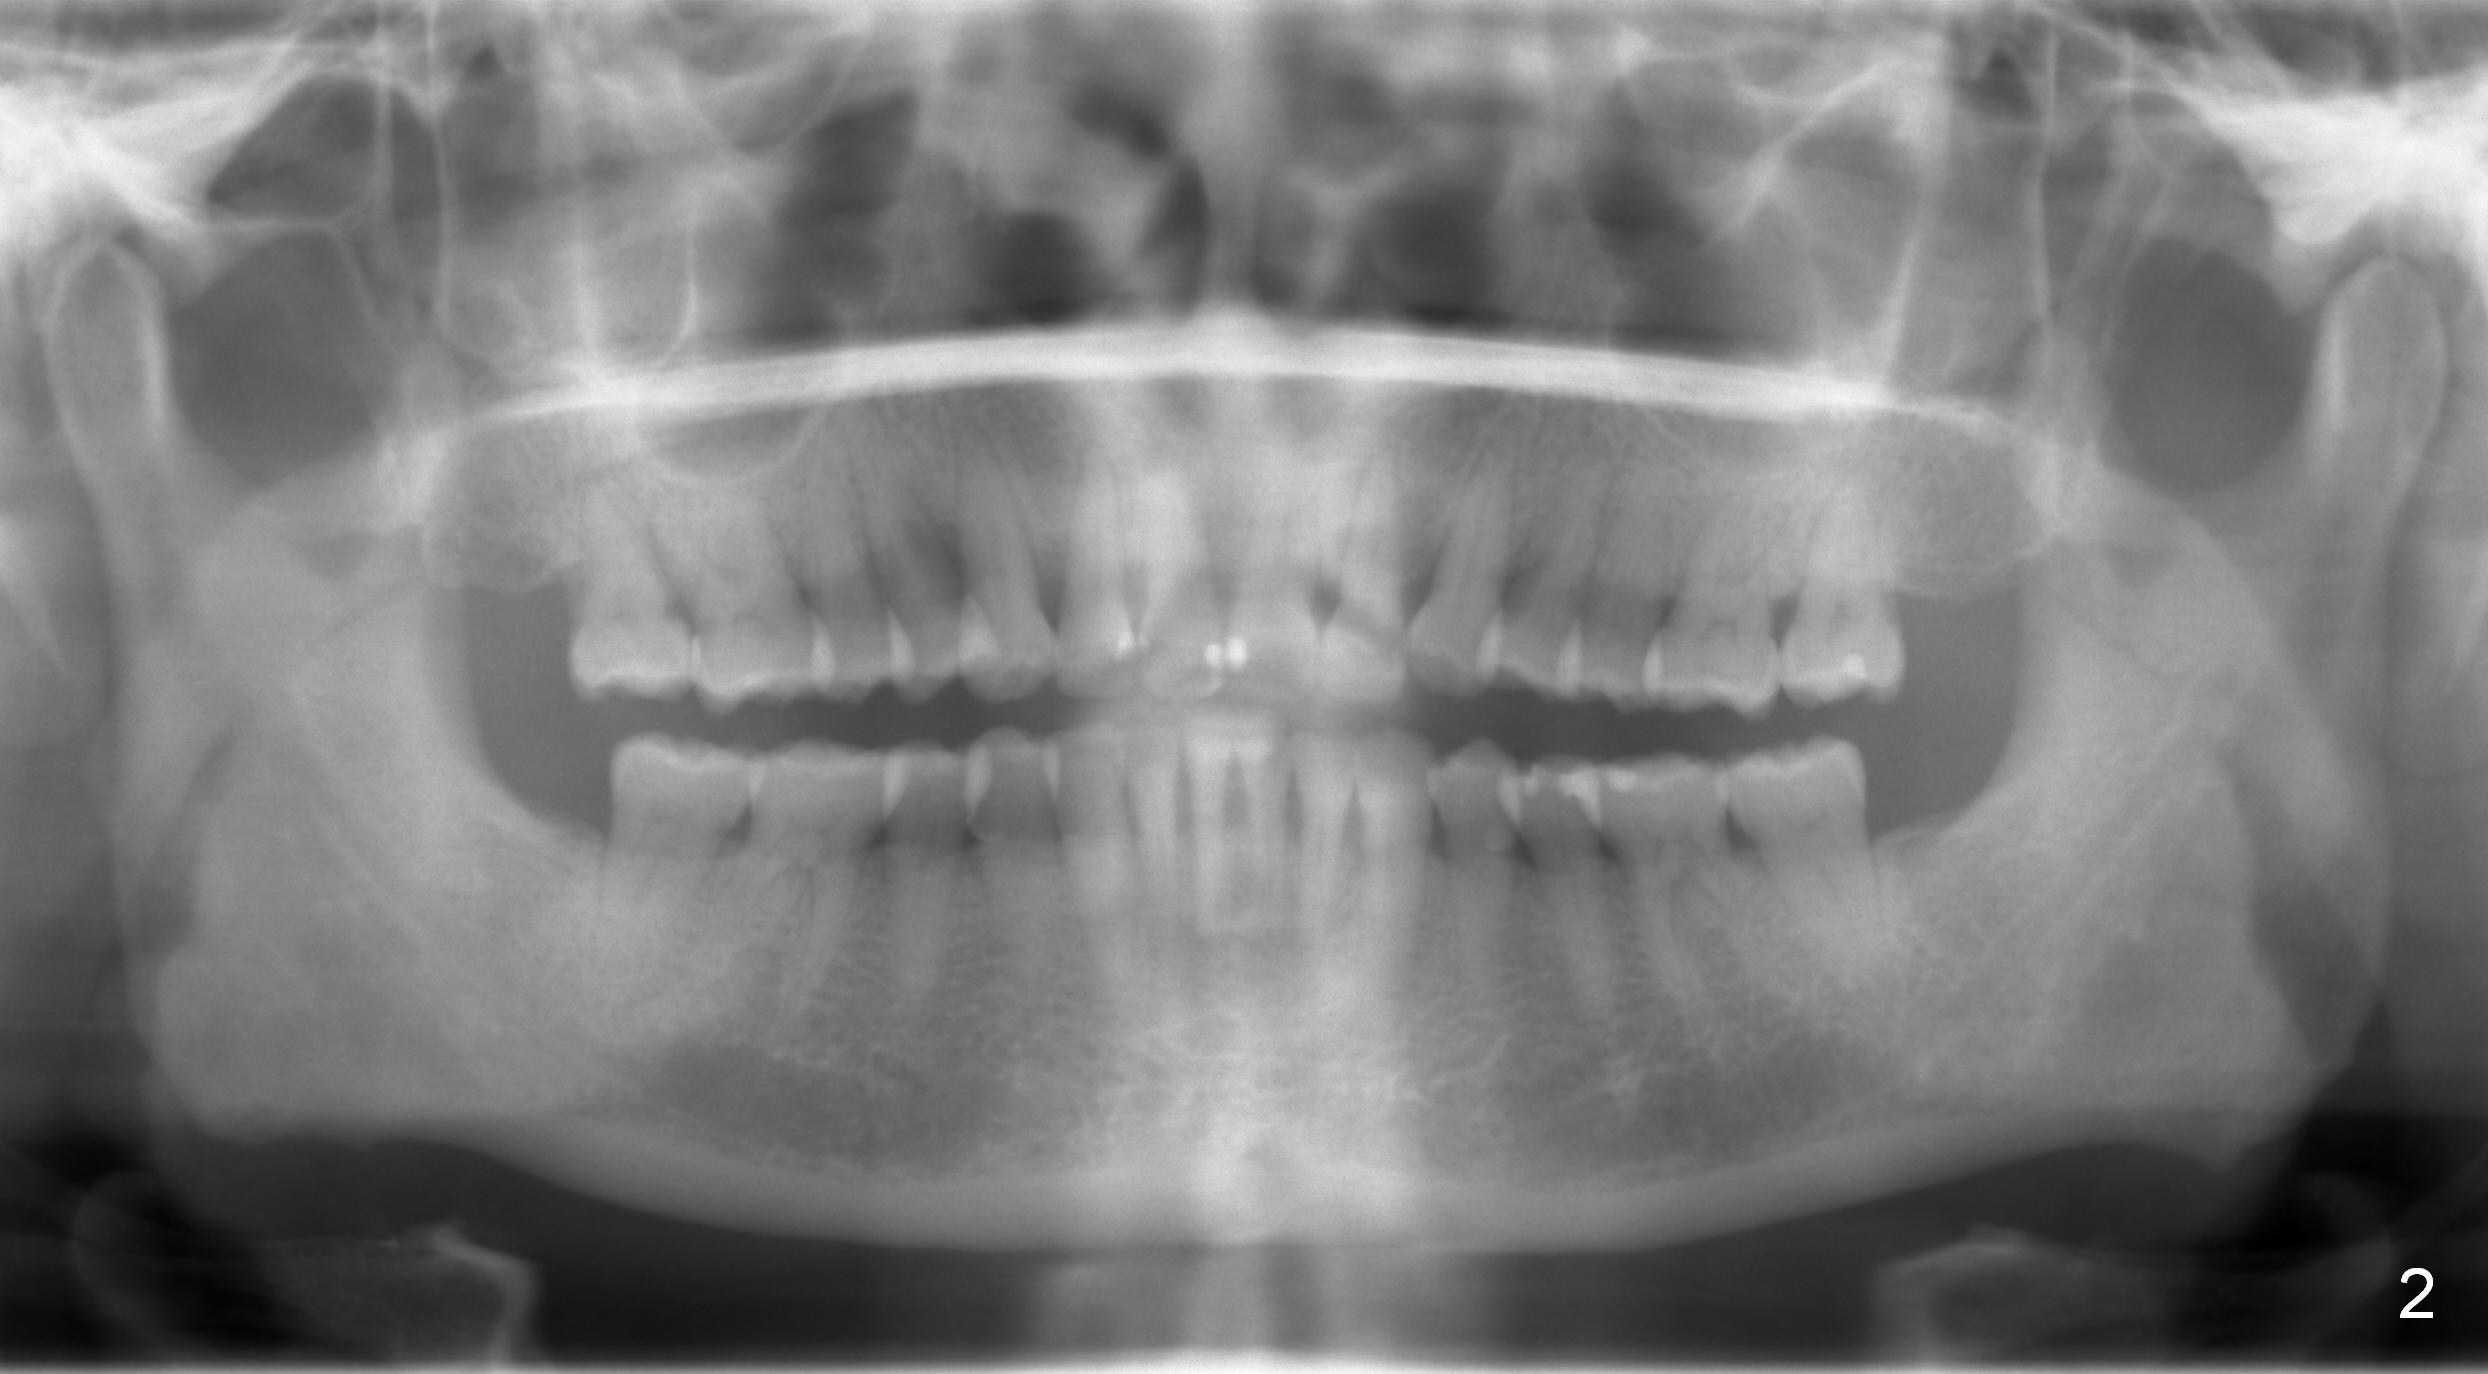

A 54-year-old lady has history of chronic periodontitis, characterized by bone loss (Fig.1 <, 2) . Her oral hygiene is fair. Bone loss and obliterated canals at #14 (Fig.1) are apparently related to bruxism. The latter seems to cause crack tooth at #15 with infection lately (Fig.3). Since the bone height is plenty (Fig.4), the longest implant will be used (5-7x20 mm (tissue-level) or 5.5x13 mm or longer (bone-level, Fig.5)). Use 2 mm drill to measure the socket (Metronidazole) depth and osteotomy will be at least 6 mm in the new bone. In fact, the tooth #14 is found to be affected when the patient returns from a periodontist's office (Fig.3).